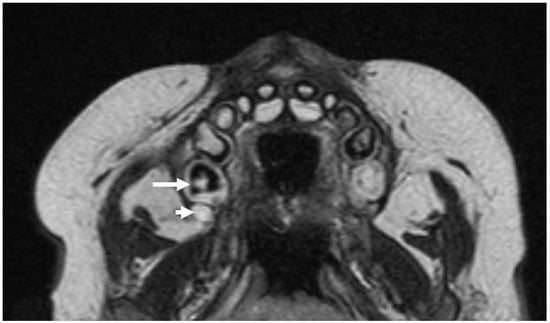

3.5.4. Periodontal Disease Radiologic Correlations

3.3. Radiologic Correlations of Embryological Development